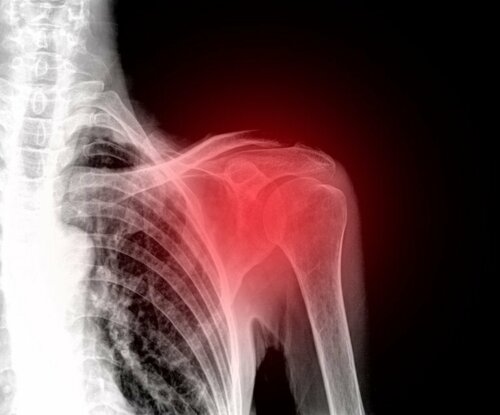

Die Frozen Shoulder ist eine pathologische und traumatologische Erkrankung der Schultergelenkkapsel. Man bezeichnet diese Krankheit auch als adhäsive Kapsulitis, da die Entzündung mit Verklebungen und Verwachsungen der Schulterkapsel einhergeht. Weitere Bezeichnungen dieses Krankheitsbildes sind Humerocapsulitis adhaesiva, Capsulitis fibrosa oder fibröse Schultersteife.

Um diese Krankheit zu verstehen, gehen wir zuerst näher auf die Anatomie der Schulter ein. Das Schultergelenk umfasst den Oberarmknochen (Humerus), das Schlüsselbein (Clavicula) und das Schulterblatt (Scapula), die von einer schützenden Gelenkkapsel (Capsula arcicularis) umgeben werden. Diese Gelenkkapsel stabilisiert das Schultergelenk und ist außerdem für die Bildung der vom Gelenkknorpel benötigten Gelenkflüssigkeit zuständig. Bei einer Frozen Shoulder kommt es zu einer Entzündung dieser Gelenkkapsel.